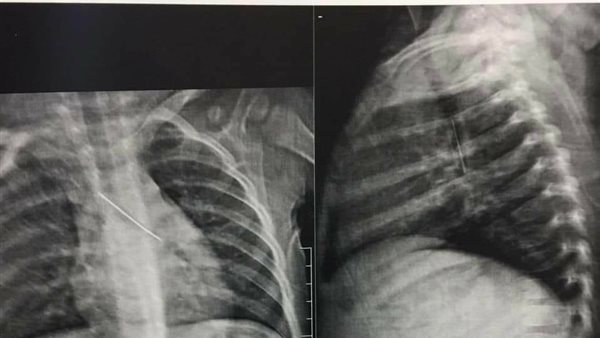

ومن ناحيته أوضح الدكتور إبراهيم قصب رئيس قسم جراحة القلب والصدر، أنه تم على الفور استقبال الطفل وإجراء أشعة له والتي أوضحت أن الدبوس الذي ابتلعه اشتبك بالرئة واستقر بالقصبة الهوائية وعلى الفور تم تجهيز الطفل للجراحة، وتم إجراء المنظار فورا واستخراج الدبوس الذي وجد أنه طويل نسبيًا مقارنة بطول القصبة الهوائية لعمر هذا الطفل الصغير.